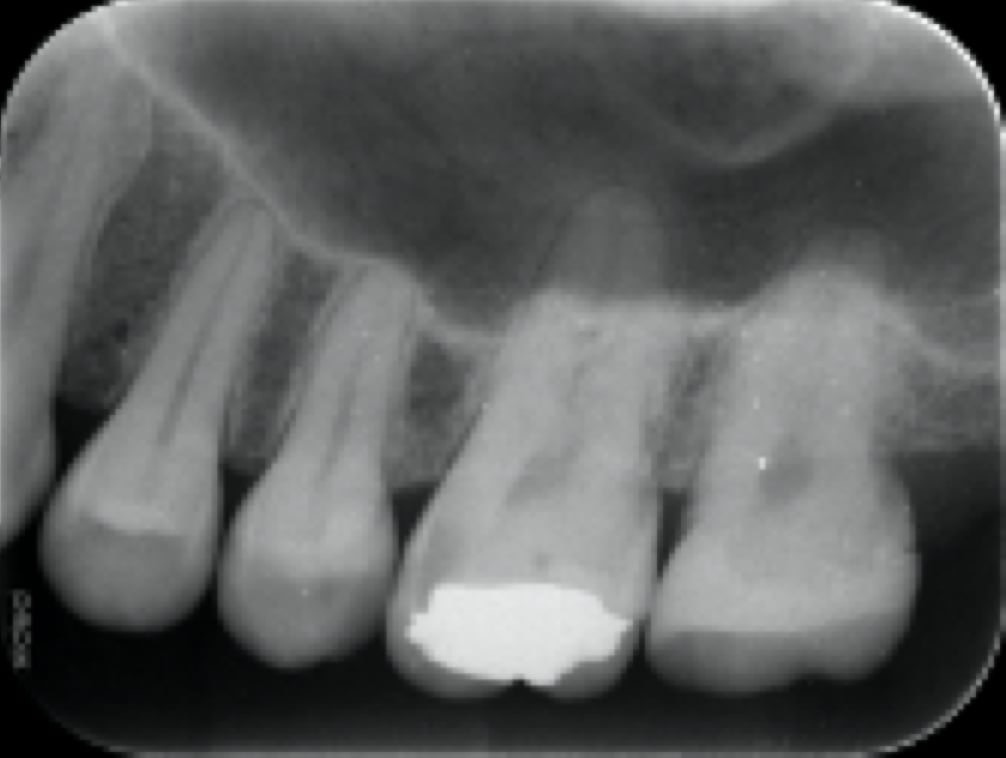

外科的歯内療法(根の先を切断して逆から塞ぐ外科手術)

根管治療では治らない場合もしくは諸事情により被せ物を外して再治療できない場合に外から切って治す外科手術です。

紹介時(再根管治療)

再根管治療終了

治癒せず腫れが再発

外科手術(根の先を切断)

手術後3ヶ月(治癒)